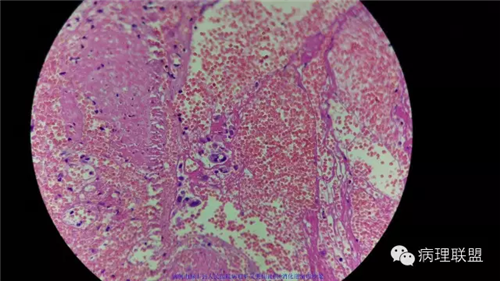

病例1

病史

男性,46岁。慢性胆囊炎急性发作。

(注:病例由禄丰县人民医院病理科吴美仙提供 致谢!)